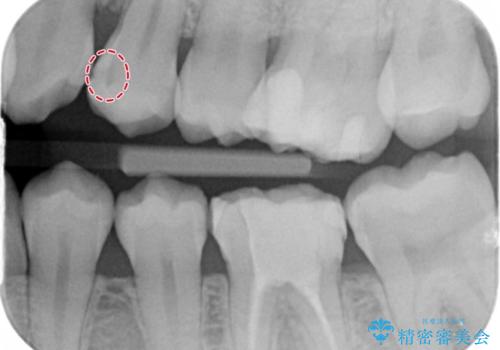

- 外から見える範囲の銀歯のやり替えをご希望で来院されました。

セラミックインレーでの治療となります。

奥歯とはいえ今回のようなケースでは笑った時に銀歯がちらつきます。

白く目立たないセラミックインレーが入ったことで大変喜んでいただけました。